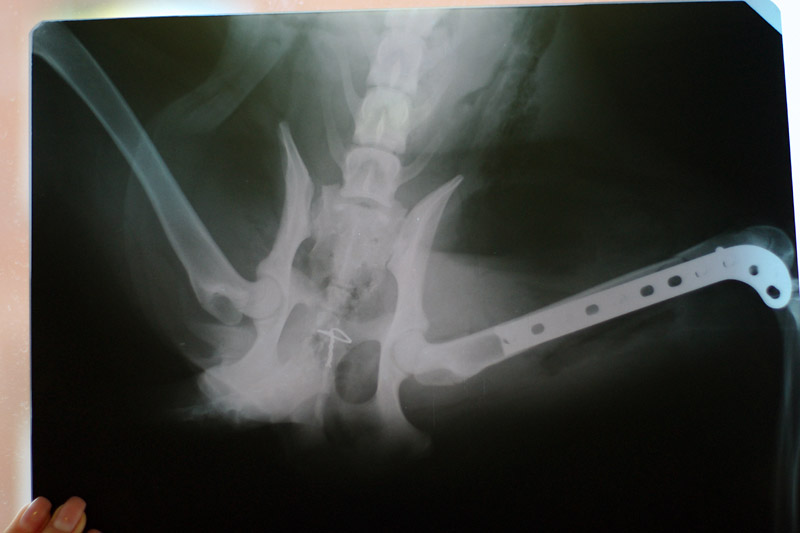

Сейчас девочка у меня, на завтра назначен рентген в ЦВК. По результатам будет приниматься решение о дальнейшей судьбе.

Сначала решили везти ее в приют, но там уже хватает подобных пациентов. Если понадобится операция, приюту это не потянуть.